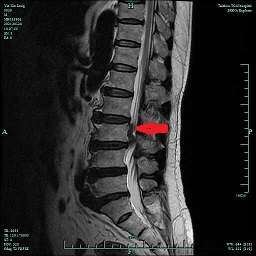

前段時間,臺州市中醫(yī)院就來了一名“腰椎間盤突出癥”患者。59歲的尹先生自訴有“腰椎間盤突出癥”病史10余年,住院前3天突然出現(xiàn)明顯的左側(cè)腰腿痛,久坐或走路時疼痛劇烈,難以忍受,“感覺自己左側(cè)大腿內(nèi)側(cè)的肉都是死的,一點感覺都沒有,會不會癱瘓了?”這可把尹先生嚇得不輕,以為自己是中風(fēng)了,馬上入住了醫(yī)院神經(jīng)內(nèi)科,后來做了腰椎磁共振,MR提示:腰3∕4椎間盤向上脫垂,壓迫相應(yīng)節(jié)段左側(cè)神經(jīng)根。經(jīng)骨科顏峰主任會診后,轉(zhuǎn)入骨科擬行“椎間孔鏡下髓核摘除術(shù)”。

5月28日,顏峰主任順利地為尹先生實施了“椎間孔鏡下腰3∕4脫出髓核摘除術(shù)”,術(shù)中取出一塊完整的髓核,術(shù)后即刻患者腰腿痛、大腿內(nèi)側(cè)的麻木基本消失。